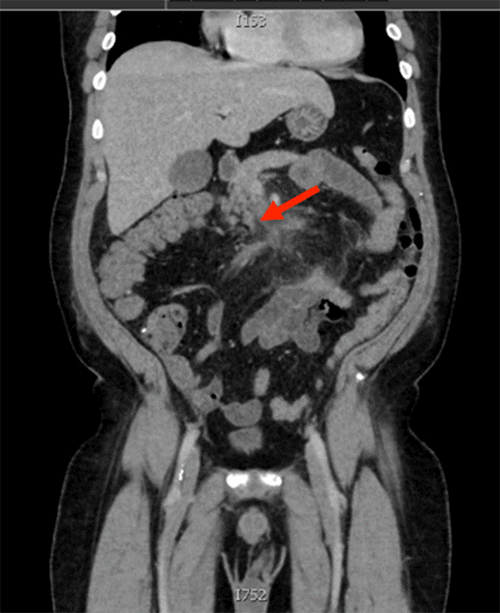

On POD 20, the patient developed a fever and tachycardia that worsened overnight. A CT angiogram was ordered to rule out pulmonary embolus or bowel ischemia. The scan revealed a persistent filling defect within the SMV and worsening retroperitoneal inflammation (Figure 3). There were no signs of bowel compromise, perforation, or progression of the thrombus into the portal vein. Based on these findings, a diagnosis of pylephlebitis of the SMV secondary to the previous appendicitis was established.

Figure 3. SMV Thrombosis with Worsening Retroperitoneal Inflammation. Published with Permission